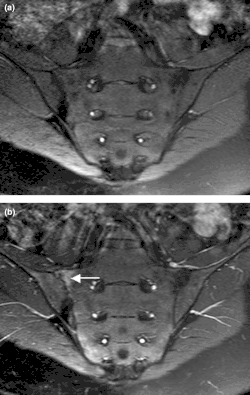

| Bone scintigraphy made with 99mTc demonstrating the highly enhanced tumor borders and the left elbow affected by psoriatic arthritis. | |